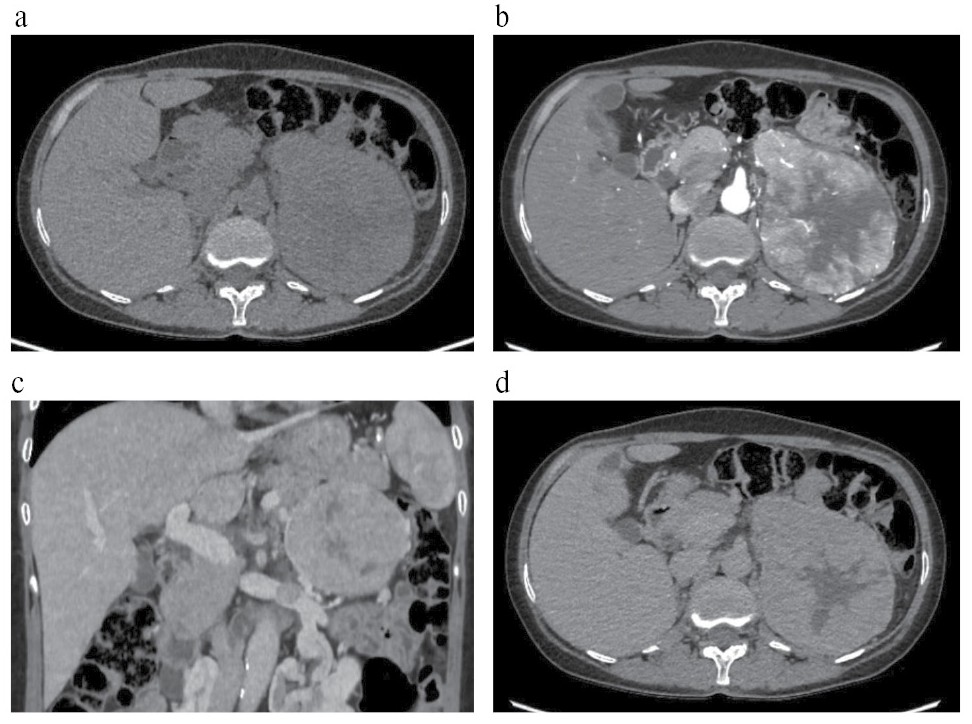

При визуальной оценке КТ-изображений ФХЦ отмечались различия по структуре и характеру контрастирования образований без связи с размерами (рис. 1–3).

Рис. 3. КТ с КУ: ФХЦ левого надпочечника размерами 120×100 мм, неоднородной структуры, с опухолевым тромбом в надпочечниковой вене: a – NAT: плотность образования 39 ед.Н, с наличием в центральных отделах гиподенсной зоны, плотностью 21 ед.Н; b – ART: образование накапливает контрастный препарат до 132 ед.Н, с сохранением гиподенсной зоны в центральных отделах, не накапливающей контрастный препарат; c – VEN, корональный срез: плотность образования 109 ед.Н, в просвете левой почечной вены визуализируется опухолевый тромб, пролабирующий из левой надпочечниковой вены; d – DEL: образование «сбрасывает» контрастный препарат до 75 ед.Н.

Fig. 3. Contrast-enhanced CT: PCC of the left adrenal gland of 120×100 mm, with heterogeneous structure and a tumor thrombus in the adrenal vein: a – NAT: density of the mass is 39 HU, with a hypodense zone in the central parts of 21 HU; b – ART: the mass uptakes the contrast agent up to 132 HU, with the preservation of the central hypodense zone that does not uptake the contrast agent; c – VEN, coronal section: density of the mass is 109 HU, a tumor thrombus prolapsing from the left adrenal vein is visualized in the lumen of the left renal vein; d – DEL: the mass releases the contrast agent up to 75 HU.